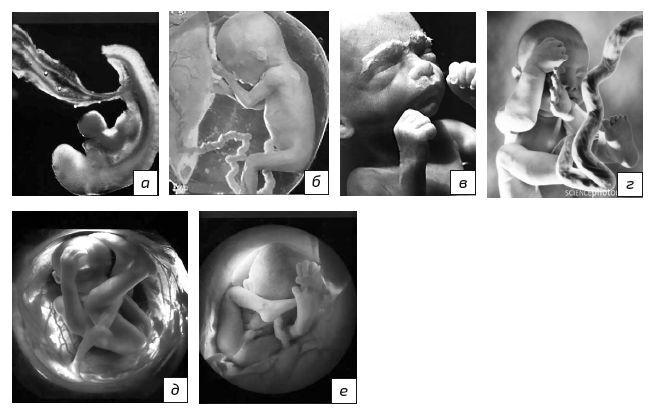

3. Эмбриональный период длится 5–6 недель. Питание зародыша осуществляется из зародышевого мешка. Происходит закладка и органогенез почти всех внутренних органов будущего ребенка (рис. 1.3а). Воздействие тератогенных факторов вызывает эмбриопатии, которые представляют собой наиболее грубые анатомические и диспластические пороки развития.

4. Неофетальный (эмбриофетальный) период продолжается 2 недели. В это время формируется плацента, что совпадает с окончанием формирования большинства внутренних органов, кроме центральной нервной и эндокринной систем. Правильное формирование плаценты определяет дальнейшую интенсивность роста плода.

5. Фетальный период (ранний и поздний) продолжается от 9 недель до рождения, при котором развитие плода обеспечивается гемотрофным питанием (через сосуды плаценты).

Ранний фетальный подпериод (от начала 9-й до конца 28-й недели) характеризуется интенсивным ростом и тканевой дифференцировкой органов плода (рис. 1.3б и 1.3в). Ранние фетопатии характеризуются задержкой роста и дифференцировки органов (гипоплазия) или нарушением дифференцировки тканей (дисплазия). Ответ на инфекцию выражается соединительнотканными пролиферативными реакциями, приводящими к циррозам и фиброзам. Иногда рождается незрелый либо недоношенный ребенок.

Рис. 1.3. 4-я неделя: дробление зиготы, имплантация, образование зародыша, зачатков важнейших органов и зародышевых оболочек; на 3-4-й неделе начинает биться сердце; на 6-й неделе плод двигает головкой, в б недель движется всем телом (а);

13-я неделя: ребенок слышит и видит (!) благодаря сформированному вестибулярному аппарату; функционируют все системы организма (б);

27-я неделя: тело покрыто мягким пушковым волосом и сыровидной смазкой, масса плода около 300 г, длина – 25,5 см, частота сердечных сокращений 130–150 ударов в мин. (в); 36–38 недель: длина плода 45–48 см, вес 2200–2400 г; жизнеспособен, громко кричит, открывает глаза, выражен сосательный рефлекс (г);

39-40 недель: длина 48–52 см, вес 3000–3800 г (д – девочка, е – мальчик).

Поздний фетальный подпериод начинается после 28-й недели беременности и длится до начала родов, т. е. до отхождения околоплодных вод (рис. 1.3 г).

6. Поздний фетальный подпериод переходит в интранатальный этап (рис. 1.3д и 1.3е), который исчисляется от времени появления регулярных родовых схваток до момента перевязки (пережатия) пуповины (обычно от 2 до 18 ч.).